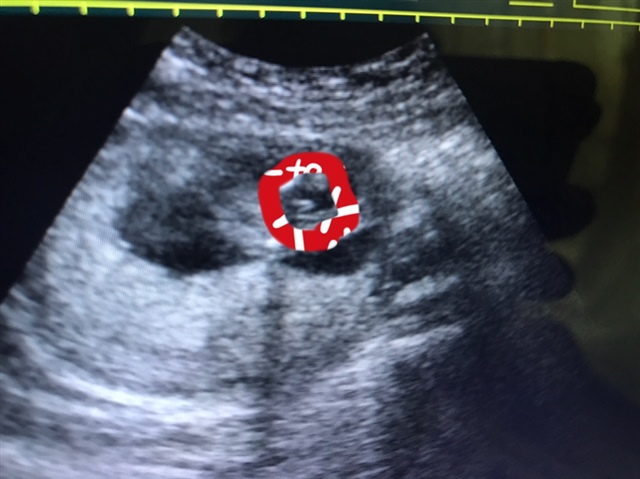

宝宝21天

是小鸡鸡,我检查男孩就是这样的

TST😘Monstar🐶(招代理)[帖主]:真的吗?我又怕不是,一个医生说是男的,一个说是女的,好迷茫

这是系带吧

TST😘Monstar🐶(招代理)[帖主]:我也不知道啊,我也好迷茫

是男的

TST😘Monstar🐶(招代理)[帖主]:怎么看的

几周做的

TST😘Monstar🐶(招代理)[帖主]:14周